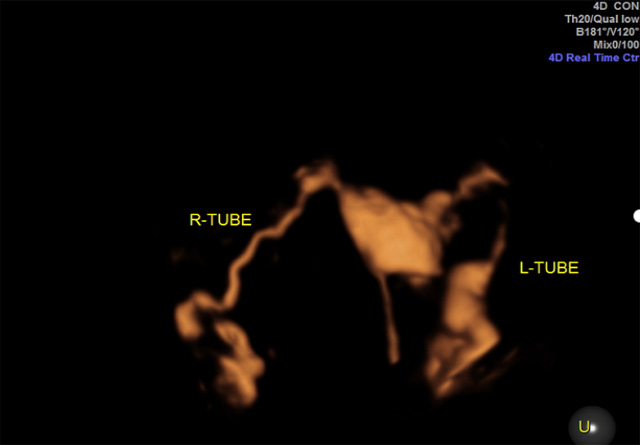

左側(cè)輸卵管通暢,右側(cè)輸卵管堵塞